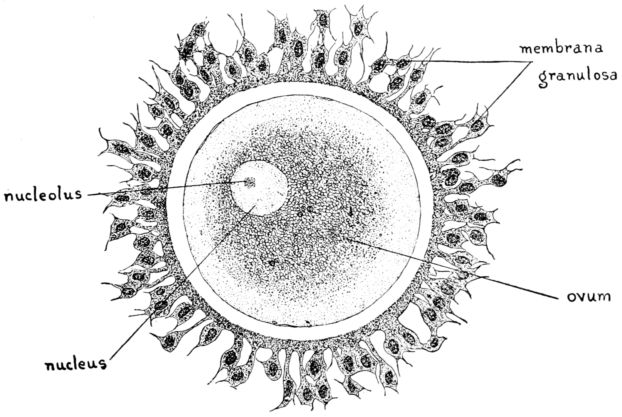

16. Diagram of human ovum 47

The ovary, the sex gland of the female, is a small, tough ductless gland, about an inch long and three-quarters of an inch wide, or about the size and shape of an almond. It is greyish pink in color and presents a more or less irregular, dimpled surface. An ovary is suspended on either side of the uterus, in the posterior fold of the broad ligament, by which it is partly covered. Its outer end is usually attached to the longest of the fimbriated extremities of the Fallopian tube, the fimbria ovarica, which has the form of a shallow gutter, or groove. The inner end of the ovary is attached to the ovarian ligament, which in turn is attached to the uterus below and behind the tubal entrance.

The ovary consists of two parts, the central part or medulla, composed of connective tissue, nerves, blood and lymph vessels, and the cortex, in which are embedded the vesicular Graafian follicles containing the ova. At birth each ovary contains upwards of 50,000 of these ova, which are the germ cells concerned with reproduction and the process of menstruation.

These ovarian glands perform two vital functions, for in addition to their prime function of producing and maturing the germinal cell of the female, they provide an internal secretion 35which exercises an immeasurably important, though imperfectly understood, influence upon the general well-being of the entire organism.